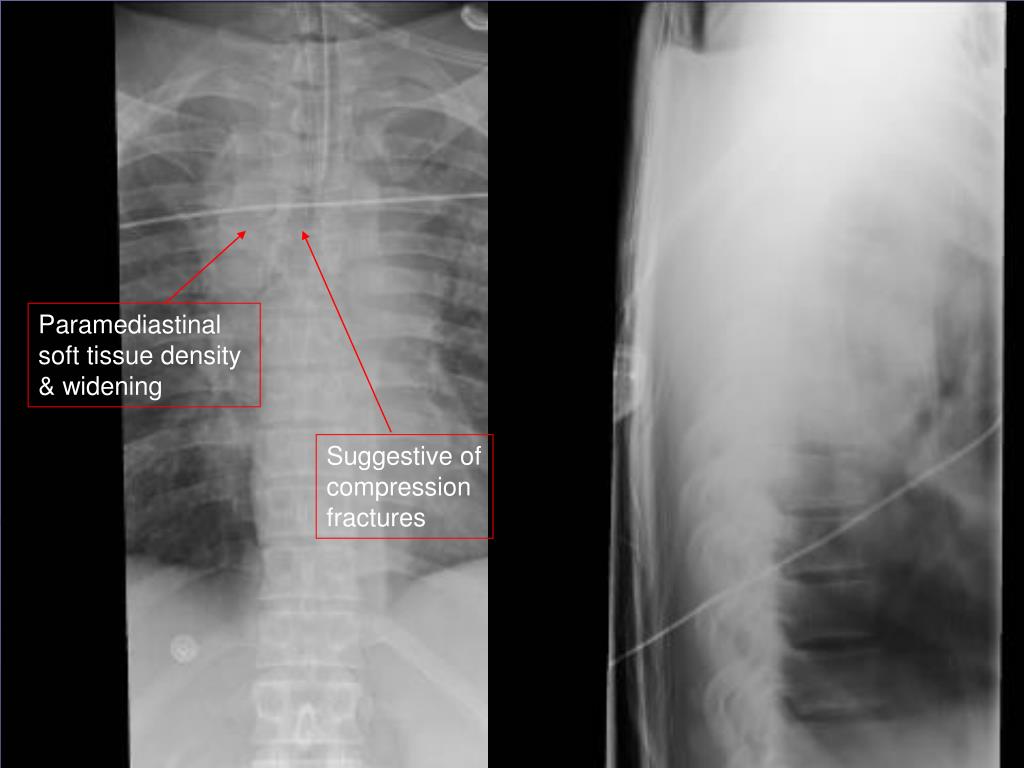

23. Case 5 • 29 yo driver offroading in pick-up truck – rolls it at speed • Not belted, ejected from vehicle and trapped underneath for 3 hrs

24. Paramediastinal soft tissue density & widening Suggestive of compression fractures